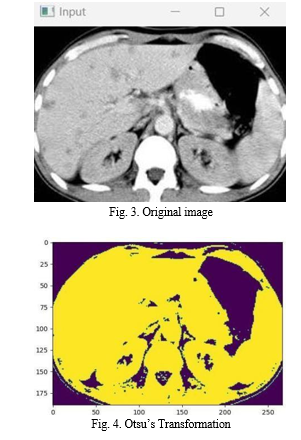

Here in this project we used Otsus method.

Otsu's method is a widely used automatic thresholding technique in image processing, which involves separating the foreground and background pixels of a grayscale image based on their intensity values to produce a binary image.

Otsu's method is a widely used automatic thresholding technique in image processing, which involves separating the foreground and background pixels of a grayscale image based on their intensity values to produce a binary image. The Otsu's method calculates the ideal threshold value by maximizing the variance between the two categories of pixels - foreground and background. This method assumes that the image has two classes of pixels, namely the object and background, and that the gray level histogram of the image is bi modal.

To find the optimal threshold value for converting a grayscale image into a binary image, the Otsu's method computes the weight, mean, and variance of the two classes of pixels, i.e., foreground and background, for each possible threshold value. Initially, the histogram of the input grayscale image is calculated. The weight of a class is the fraction of pixels in that class, while the mean represents the average gray level value of the pixels in that class.

On the other hand, the variance measures the spread of the pixel values in a class. After computing the weight, mean, and variance of the two classes of pixels (foreground and background) for each possible threshold value, the Otsu's method proceeds to calculate the between class variance.

This is accomplished by computing the weighted sum of the variances of the two classes, where the weights are the fractions of pixels in each class. The between-class variance is a measure of the degree of separation between the two classes of pixels.

After calculating the between-class variance for each possible threshold value, Otsu's method selects the threshold value that maximizes the between-class variance. This threshold value is then applied to the grayscale image to generate a binary image, where pixels with intensities above the threshold are classified as foreground, and pixels with intensities below the threshold are classified as background. The mathematical formula used in Otsu's method calculates the optimal threshold value, T, by minimizing the intra-class variance of the two regions created by the threshold. The formula for the intra-class variance is:

sigma^2_w(T) = w1(T) * w2(T) * [mu1(T) - mu2(T)]^2

where w1(T) and w2(T) are the probabilities of the foreground and background regions, respectively, and mu1(T) and mu2(T) are the mean intensities of the foreground and background regions, respectively.